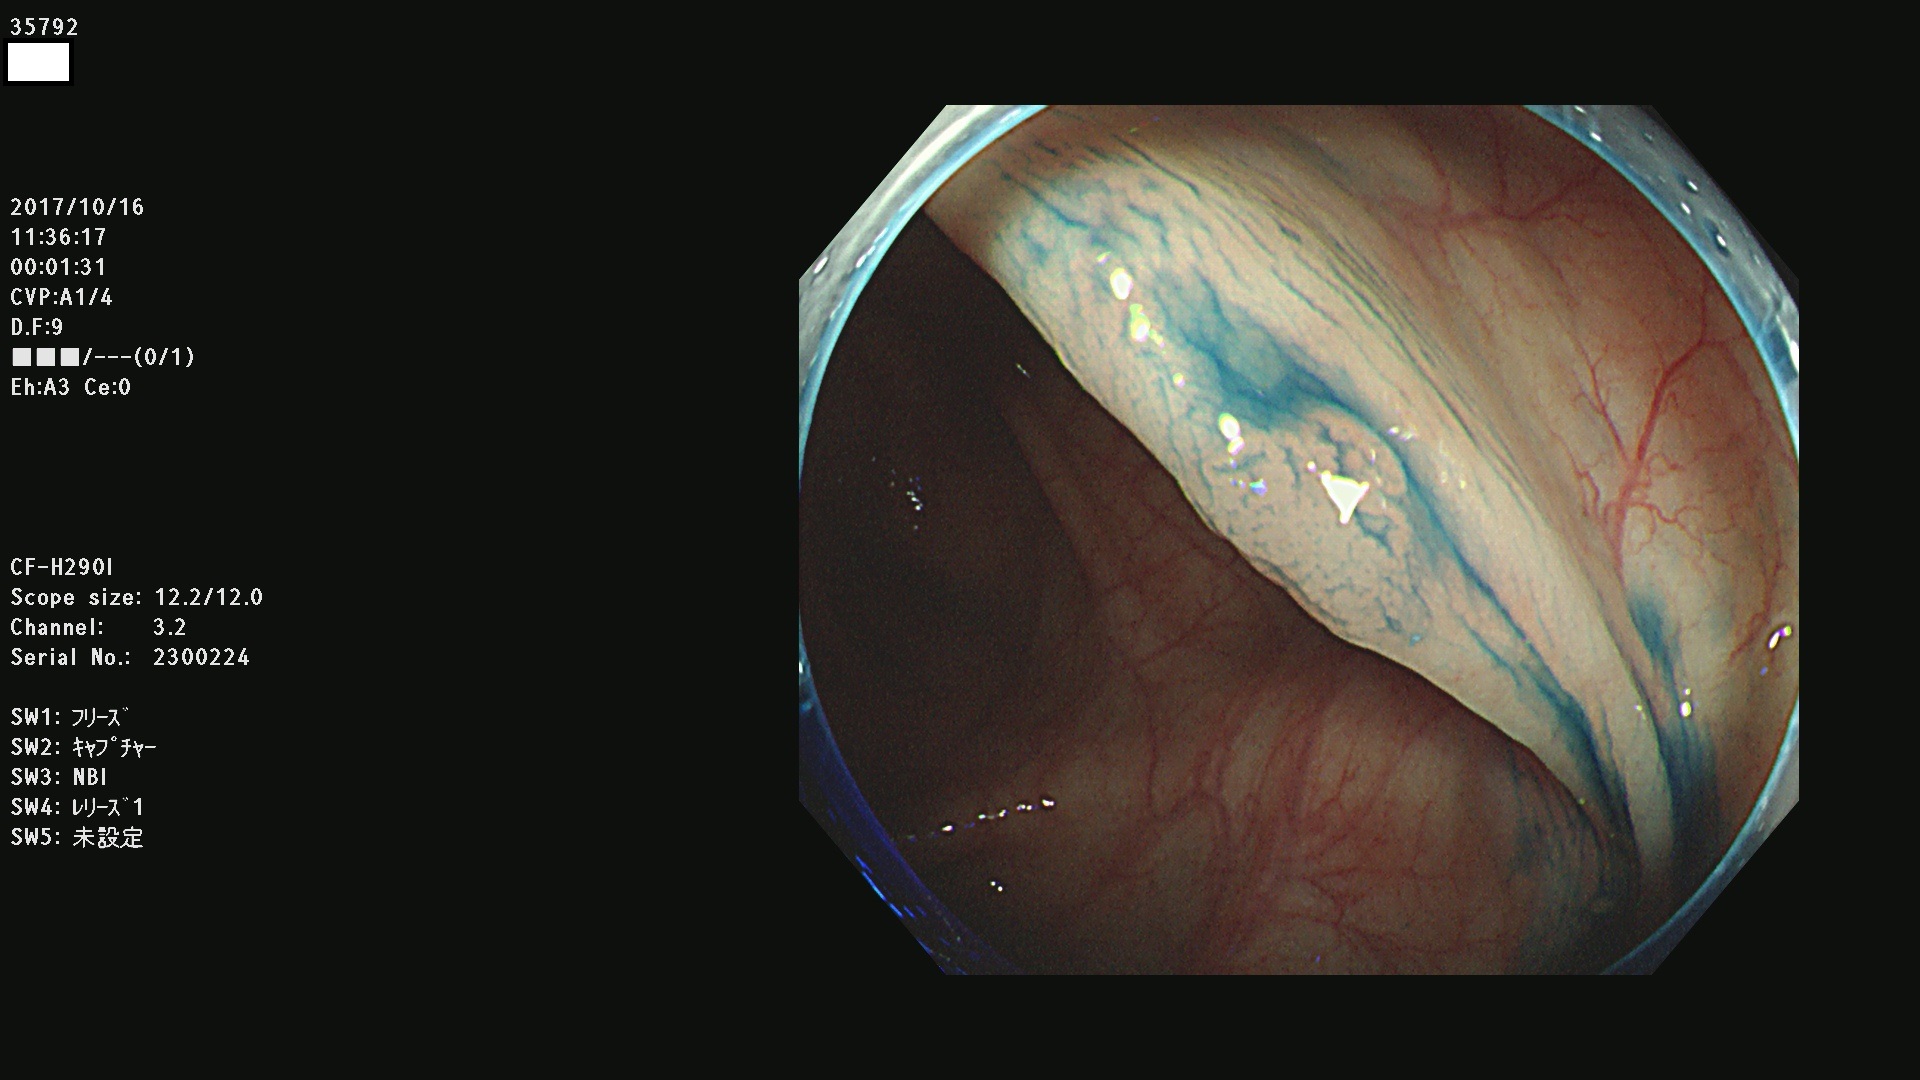

35700 35701 35704 35706 35707 35708 35709 35711(SSA/Pのみ) 35715 35716 35717 35718 35720(SSA/Pのみ) 35722 3576(SSA/Pのみ) 35730 35732 35734(SSA/Pのみ) 35736(SSA/Pのみ) 35741 35742 35743 35744 35746 35748 35749(SSA/Pのみ)35755 35757 35760 35761 35762 35763 35764 35766 35767 35770 35772(SSA/Pのみ) 35773 35781 35783 35785 35786 35787 35788 35791 35795 35796 35797 35798 35799

発見困難で危険性の高い平坦型病変(上記100名より抽出)